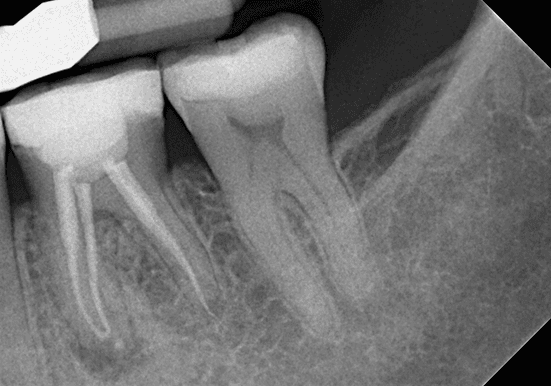

Endodontics

Is This a Case for an Apicoectomy?

While patients dread root canals, they are even less happy about losing teeth. If a conventional root canal is not an option, what else can you do to save the t...